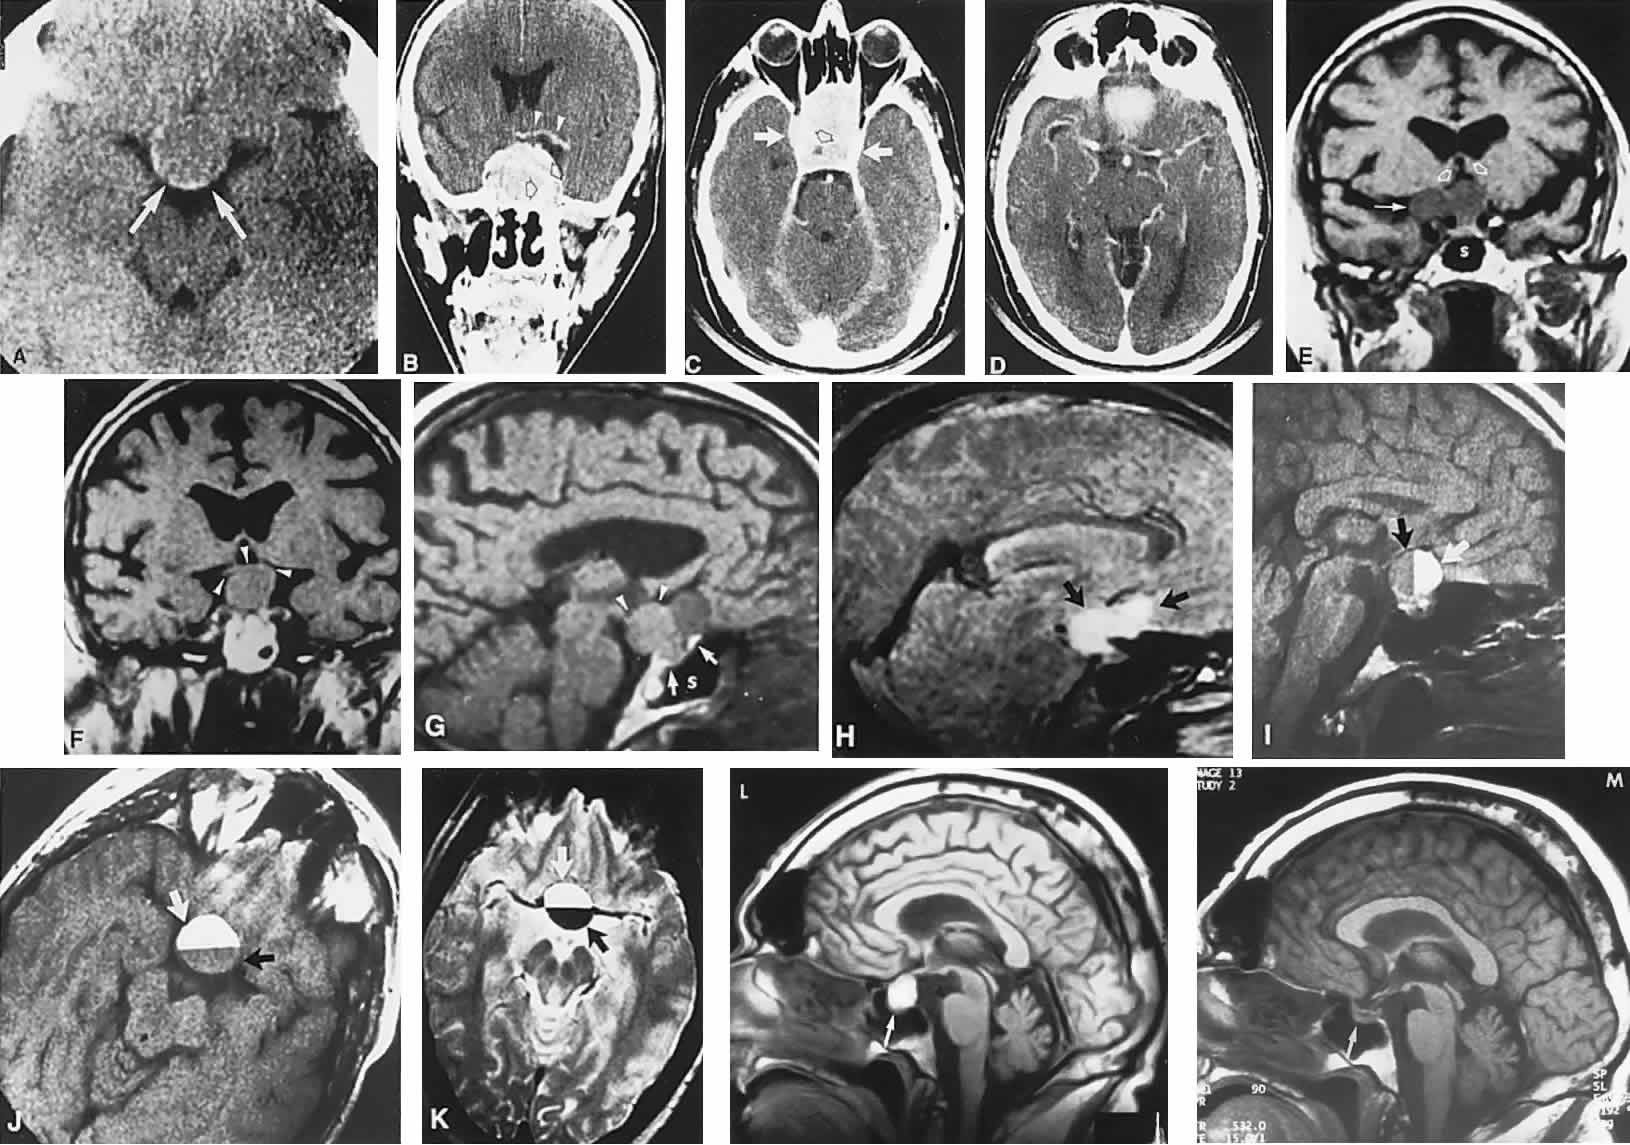

The absence of field defects, for example, in patients undergoing evaluation for amenorrhea, galactorrhea, or sellar enlargement incidentally discovered, does not imply the absence of an adenoma. Obviously, patients with microadenomas, that is, confined within the sella, do not have field defects. From a study24 of 50 cases of pituitary adenomas with chiasmal syndrome, it was concluded that visual disturbance occurs when the chiasm is displaced approximately 10 mm upward (see also Volume 2, Chapter 4, Fig. 6). The modern management of pituitary adenomas should involve several disciplines: current neuroradiologic studies detect microadenomas and provide precise delineation of gross morphology and status of neighboring structures, and mixed MRI signals suggest new or old hemorrhage, cysts, and so forth (Fig. 2); radioimmunoassay techniques assay PRL and other endocrine levels; oral neuropharmacologic agents, such as bromergocryptine, provide a “medical adenomectomy” for hyperprolactinemia and acromegaly; transsphenoidal surgery, including high-illumination microscopical procedures, televised radiofluoroscopic monitoring, and infection control, has all but replaced transcranial approaches; immunohistochemistry techniques have replaced the anachronistic tinctorial designations (e.g., chromophobe, basophilic) with a functional classification.

Fig. 2. Large prolactinoma. Original vision in the right eye (RE) was 8/200, left eye (LE) 1/200, with serum prolactin of 26,000 ng/ml and galactorrhea. Four months of bromocriptine reduced prolactin to 661 ng/ml, vision improved to RE 20/40, LE 20/50. At 3 years, vision was as follows: RE 20/30, LE 20/20; prolactin was 25.9 ng/ml. Enhanced magnetic resonance imaging. Sagittal (A) and coronal (C) images at diagnosis. Sagittal (B) and coronal (D) images at 2-year follow-up, showing dramatic shrinkage of the mass.

Fig. 3. Neuroimaging of pituitary adenomas. A. Axial computed tomography (CT) section shows a round tumor mass filling the suprasellar cistern; ring enhancement (arrows) indicates subcapsular hemorrhage. B. Contrast-enhanced coronal CT section through a large invasive adenoma. Note encasement of the carotid artery (arrows) and the position of the middle cerebral artery above (arrowheads). C. Axial CT section shows lateral expansion into the cavernous sinuses (white arrows) and a necrotic cyst (black arrow). D. Subfrontal superior extent of the mass. Note the middle cerebral arteries. E. Magnetic resonance imaging of a large lobulated prolactinoma, with suprasellar extension. Note the distortion of the third ventricle (open arrows) and extension toward the temporal lobe (long arrow); the tumor has not involved the sphenoidal sinus (s). F. Chiasm (arrowheads) is draped on the superior surface of the tumor (TR, 550 milliseconds; TE, 26 milliseconds). G. Sagittal section shows suprasellar growth with the chiasm above (arrowheads); the sella (arrows) and sphenoidal sinus (s) are normal (TR, 850 milliseconds; TE, 26 milliseconds). H. Hyperintense signal (TR, 2000 milliseconds; TE, 60 milliseconds) indicates the partial cystic character. Sagittal (I) and axial (J) sections with head tilt to the right, in case of a large cystic adenoma with an interface level between newer blood (white arrow) and older blood (black arrow) (TR, 800 milliseconds; TE, 30 milliseconds). K. Signal difference is intensified (TR, 2100 milliseconds; TE, 80 milliseconds). L. Hemorrhage (bright signal, arrow) in a pituitary adenoma with headache and bitemporal field depressions. M. Without interventions, 2-month follow-up showed spontaneous involution, with normal pituitary gland (arrow), stalk, and chiasm.

In addition to the radiologic implications mentioned previously, specific points should be emphasized. Contrast-enhanced CT and, especially, MRI have replaced all previous radiologic techniques in the detection and anatomic assessment of sellar and juxtasellar lesions. MRI has also the inherent advantage of using no radiation, nor does it require iodinated contrast injections. Although thin-section contrasted CT does indeed disclose most lesions, bone changes, and recent hemorrhage, MRI is superior in delineating distortions of optic nerves and chiasm, in displaying arteries, and in revealing fat, hemorrhage, or cyst (see Figs. 3E through M). Indeed, in a prospective study of normal volunteers, gadolinium-enhanced MRI disclosed pituitary adenomas (3 mm to 6 mm in diameter, i.e., microadenomas) in 10% of adults aged 18 to 60 years.66 T2-weighted fast spin-echo MRIs are currently the most precise sequence for demonstrating the optic nerves and chiasm, even when these structures are severely distorted by suprasellar tumor extension.67